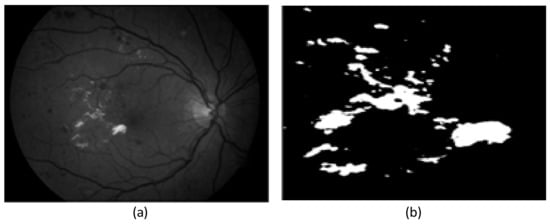

2.1. Preprocessing Based on Histogram

2.2. Preprocessing Based on Adaptive Thresholding